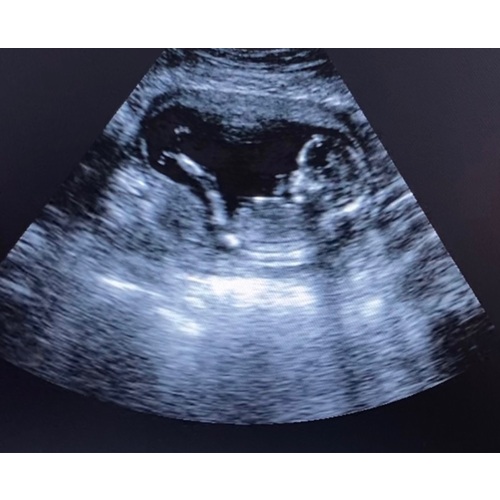

Hi ik heb de baby watcher 3 dagen gehad. Je moet niet het beste kwaliteit verwachten. Je kan niet alles duidelijk er mee zien je kan zien dat je kleine lekker beweegt en met geluk kan je het hartje zien. Bij mij was er gedoe bij het leveren op de dag zelf kregen we te horen dat die niet kwam en toen ik hem wou annuleren kon de baby watcher ineens op de post.

Mijn ervaring is als je zelf een goeie laptop hebt neem daar het pakket op zodat wellicht je beeld veel beter is je krijg hier best oudere laptops bij en de beeld kwaliteit is gewoon niet het beste. Als ik het had geweten had ik me eigen laptop genomen

Ja klopt, die krijg je er bij maar je kan ook aangegeven voor je eigen laptop tegebruiken 馃 hou er wel rekenschap mee dat melde ze mij later pas toen ik belde dat kwaliteit minder was als je plus size bent de kwaliteit slechter is.